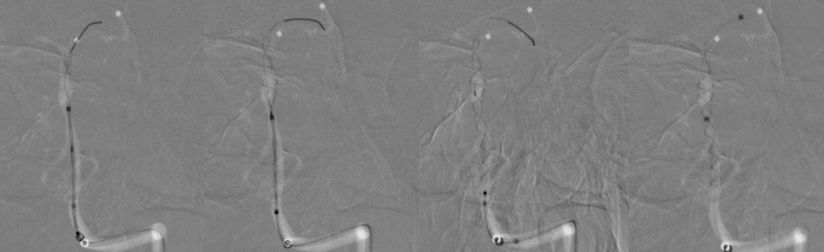

3、多个投射角度辅助下,将一枚3x35 mm的Tubridge支架经T-track支架微导管缓慢释放(图10)。

图10

4、支架完全释放后造影可见支架完全覆盖动脉瘤,贴壁良好,载瘤动脉及支架覆盖的双侧AICA及右侧椎动脉通畅(图11)。

图11